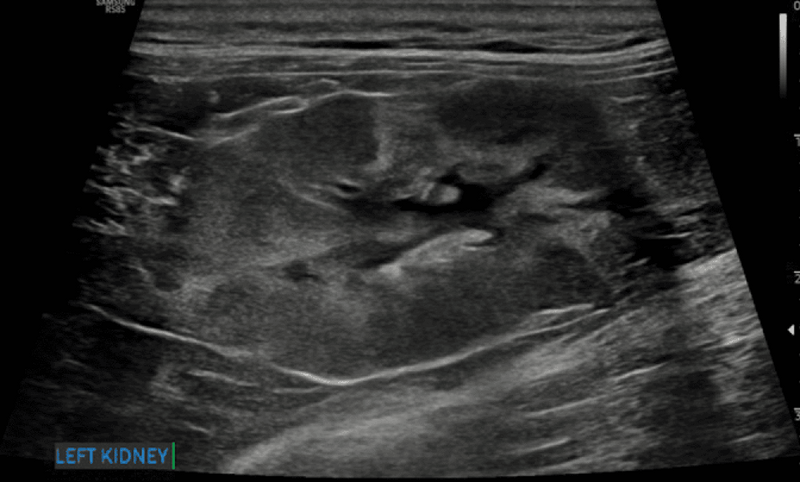

Nieregularny brzeg nerki

Nieregularne brzegi nerek (ryc. 9) mogą być związane z jednym lub kilkoma – często współwystępującymi – procesami, takimi jak zwłóknienie, stwardnienie, zanik, tworzenie torbieli albo zawał nerki.12 Nieregularny brzeg nerek jest często obserwowany w bardziej zaawansowanych stadiach przewlekłej choroby nerek i może wiązać się ze złym rokowaniem.8,15,17

Ryc. 9. Obraz w projekcji strzałkowej lewej nerki kota, ukazujący wyraźnie nieregularne brzegi związane z obecnością hiperechogeniczności kory nerki oraz przewlekłych zawałów kory nerkowej. Obecna jest także łagodna pielektazja.